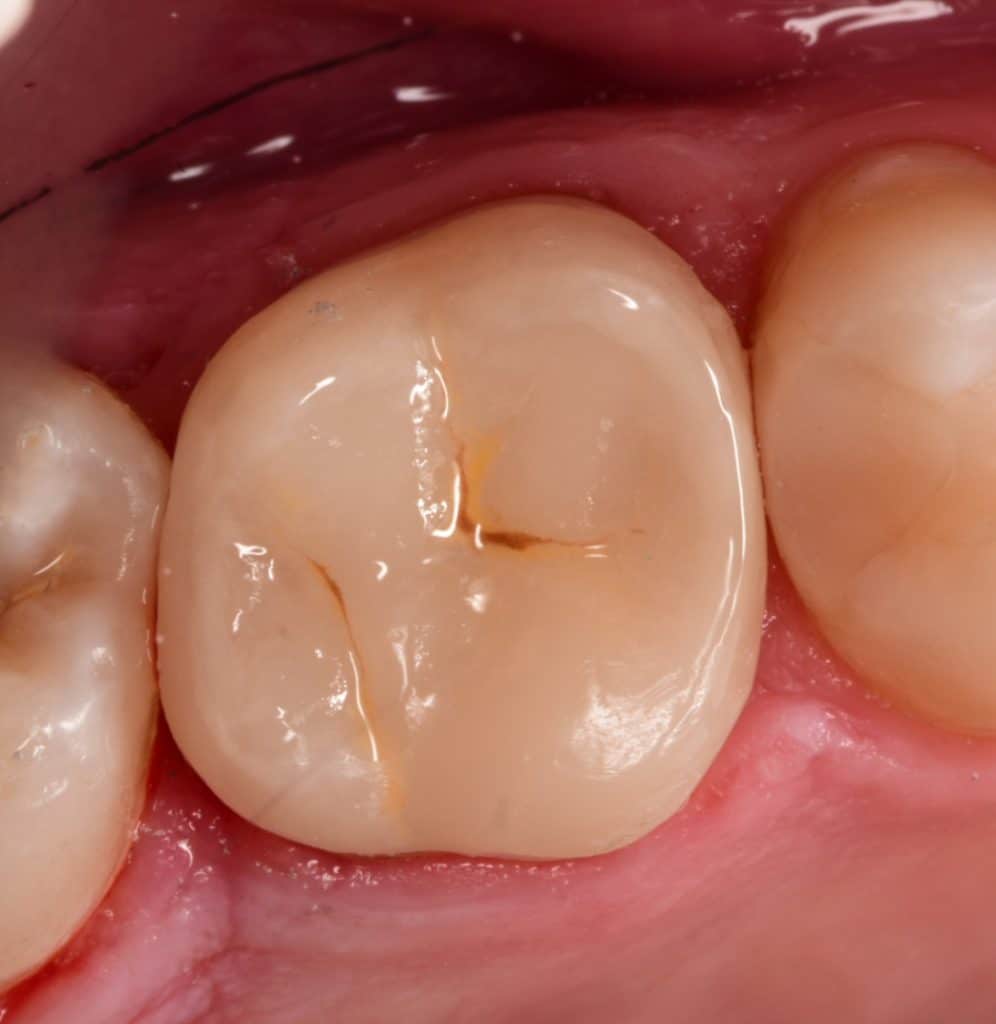

Initial situation showing large amalgam filling with open contact , the patient said that he replaced it for more than 2 times and the problem of food impaction still

Preoperative x ray